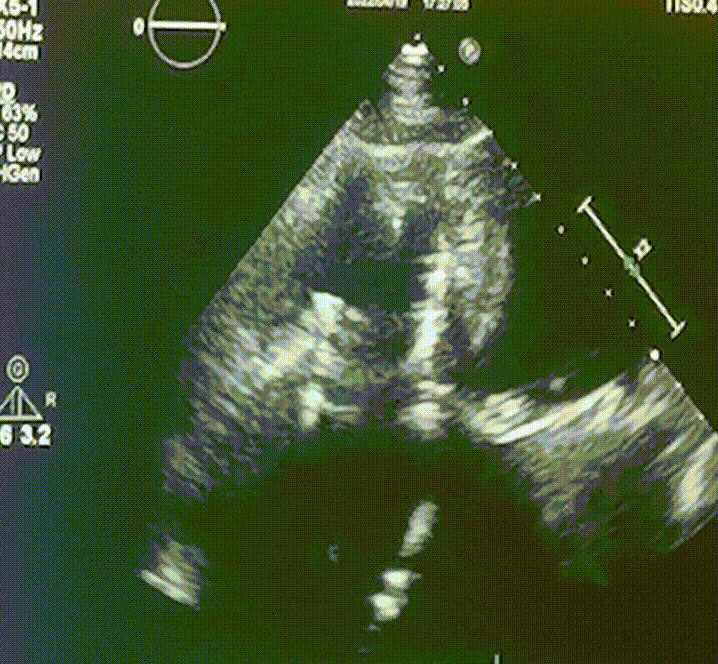

此次手術在全麻下進行,采用經(jīng)右側頸靜脈入路。術中在經(jīng)食道超聲和DSA的指引下多個維度精細調(diào)整輸送器角度,在達到正確位置后,逐步釋放瓣膜錨定裝置和盤片,最終完成瓣膜植入。術后患者右房壓明顯下降,術后超聲提示人工三尖瓣同軸性良好,瓣架固定牢靠,無反流和瓣周漏,血壓術后即刻上升20mmHg左右,手術后監(jiān)護室順利拔除氣管插管,3天后恢復良好,予以出院。

圖2.術后超聲